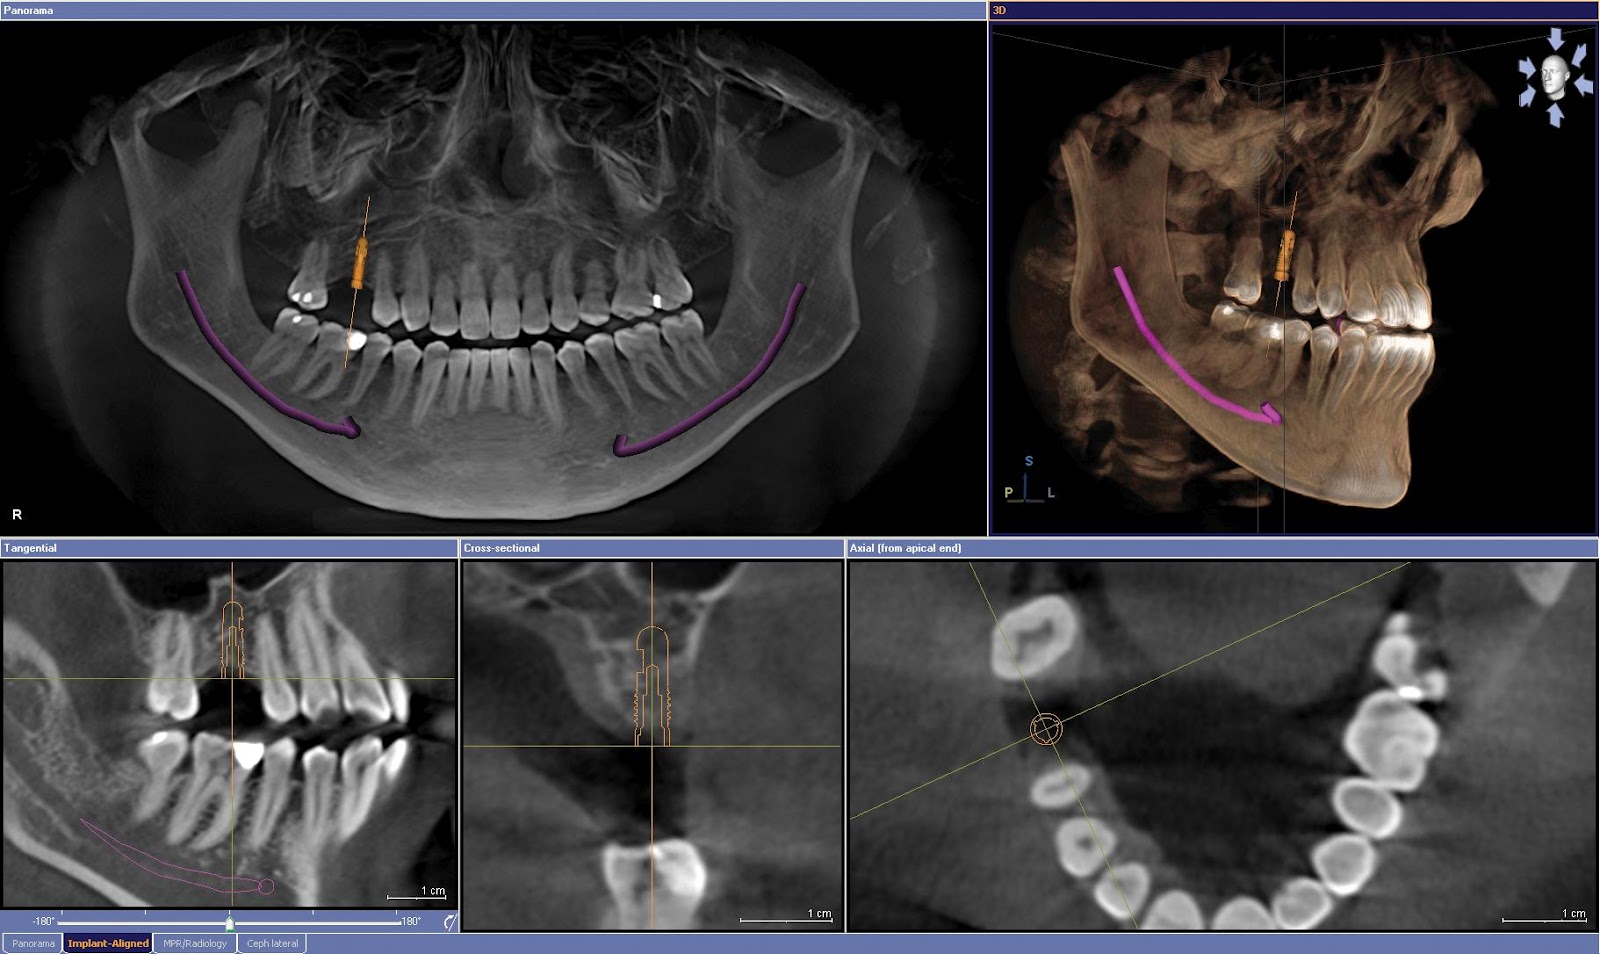

Tomografia Computadorizada Cone Bean

Z - Arco Zigomático: Apresentam-se como uma estrutura radiopaca que se estende posteriormente a partir do osso zigomático.

SN - Spto Nasal:Apresenta-se como uma estrutura radiopaca vertical e espessa. O septo nasal óssea divide a cavidade nasal em dois compartimentps, o direito e o esquerdo. O spto é formado por uma parte óssea composta pela lâmina perpendicular do osso etmóide e vômer.

PO - Palato ósseo: Apresenta-se como uma linha radiopaca horizontal estendendo-se por toda à maxila.

MAE - Meato acústico externo: Apresenta-se como uma área radiolúcida redonda ou ovóide anterior e superior ao processo mastóide.

PM - Processo mastóide do osso temporal: Aparece como uma imagem radiopaca arredondada, com áreas radiolúcida pequenas (células aéreas), localizada posterior e inferiorà região da ATM.

PE - Processo estilóide do osso temporal: Apresenta-se como uma estrutura radiopaca pintuaguda de formas e tamanhos variaods, que se estende a apartir do osso temporal anteriormente ao processo mastóide.

H - Osso hióide: Na radiografia panorâmica pode apresentar-se como uma estrutura radiopaca (às vezes sobreposta à sínfise da mandíbula), ou como duas imagens radiopacas, abaixo da mandíbula, bilateralmente.

O novo ORTHOPHOS XG 3D combina as vantagens do 2D e 3D em um só aparelho. Com uma extensa seleção de programa panorâmicos e cefalométricos, a imagem radiográfica em 2D é agora complementada com a capacidade de reconstruir as imagens em 3D. Motivos para sermos uma clínica dinâmica e atuante.